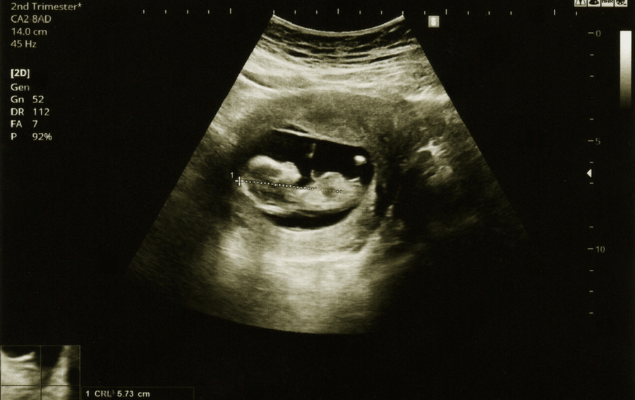

Week 13 - 26

Growth & Development Scans

Regular ultrasounds to track fetal growth, placenta health, and maternal wellness during mid-pregnancy.